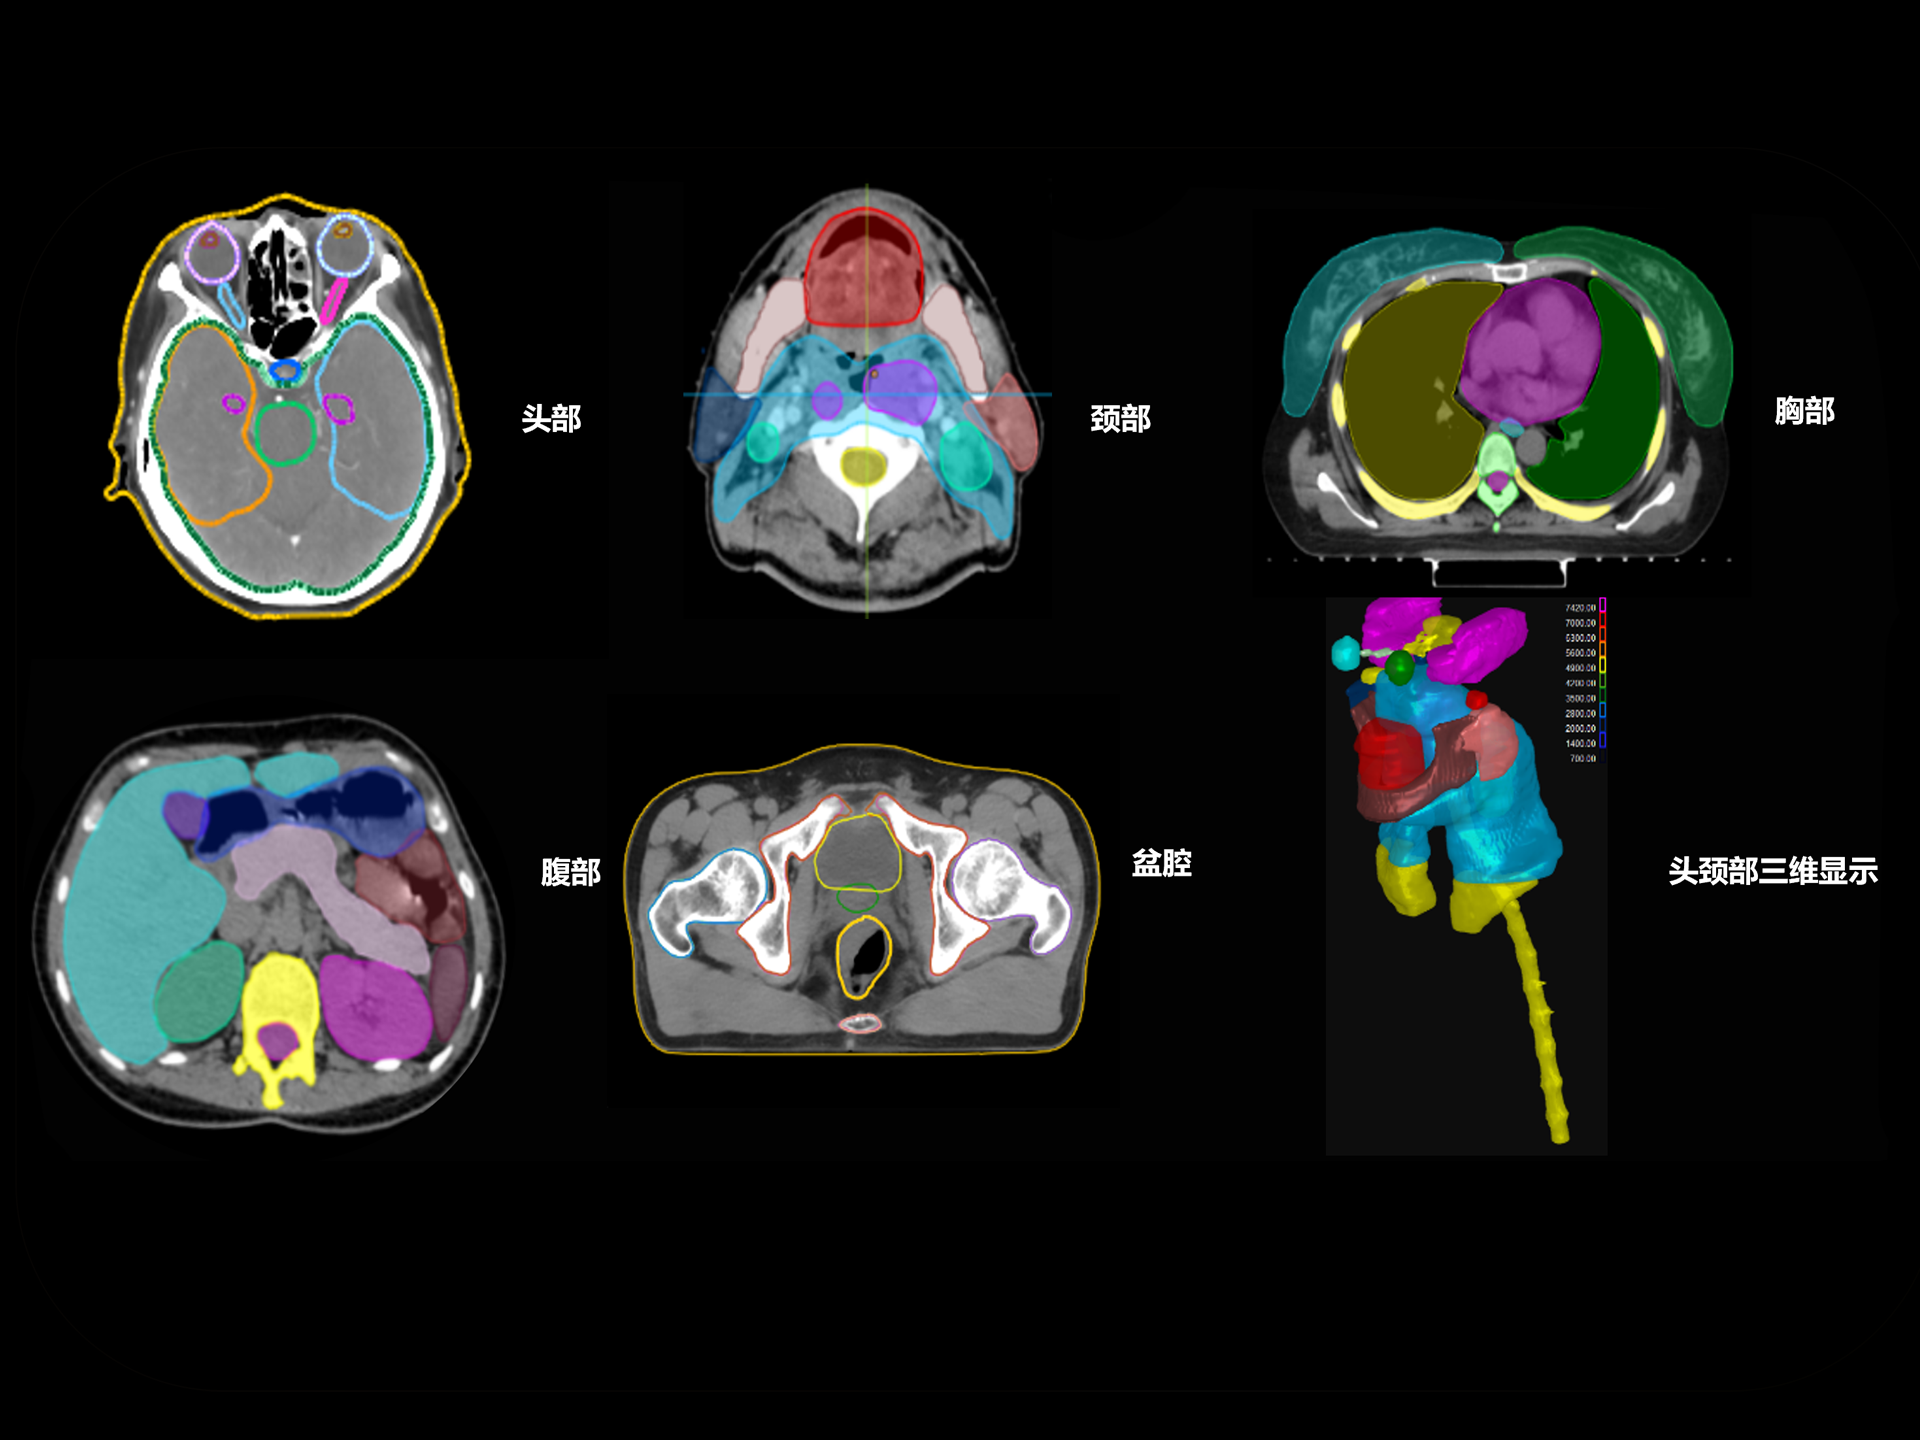

扇形束成像,极低散射,媲美CT-sim的影像品质

3mm @ 0.3% 高软组织对比度,0.55mm薄层扫描,精确鉴别肿瘤靶区边界

精准CT值,完美满足勾画、剂量计算要求

从数据源头提升图像质量,高清呈现细微变化,全面精进机载影像实力

提供传统 的CT 模拟机所一致的HU值精度(±10HU)

HU金标准